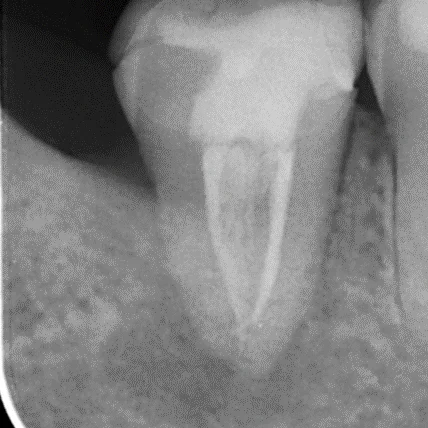

- 診斷與評估:牙醫透過X光片和臨床檢查確認受影響的牙髓狀態。

- 根管填充:用專業材料填充清潔後的根管,封閉以防微生物再次入侵。